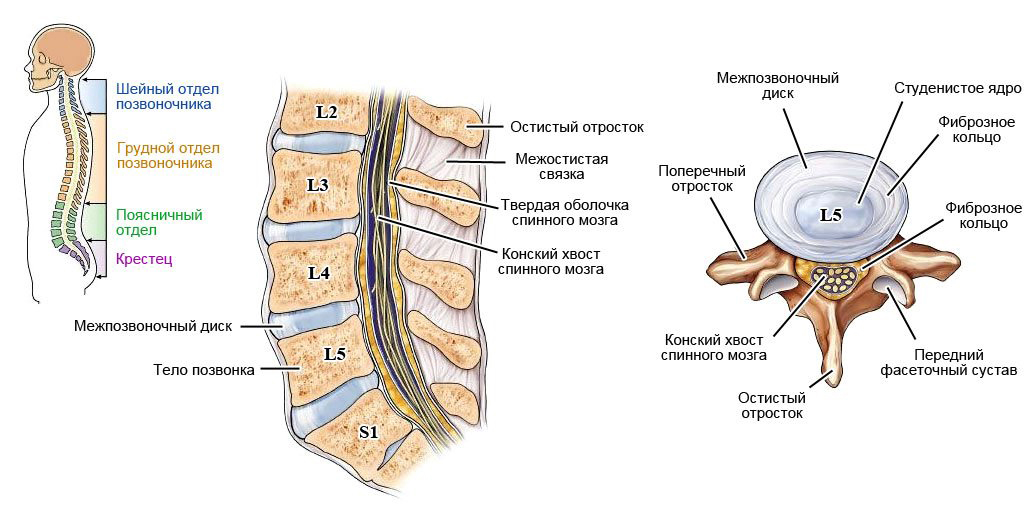

КТ-протрузии дисков: Визуализация и классификация